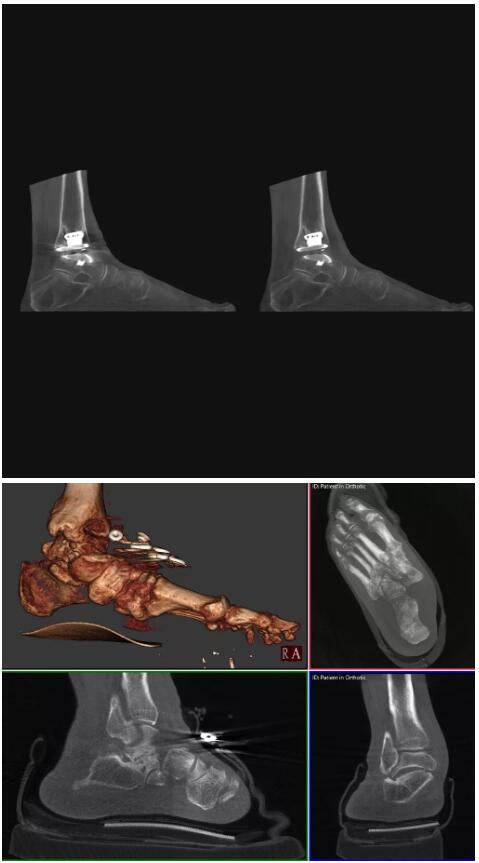

另外一款被稱為世界上最小的CT,它的重量僅300磅,不僅能夠掃查足部,還可以檢查膝蓋和上肢等。

與上面介紹的CT一樣,它同樣具有輻射低、占地空間小(23*36)的特點(diǎn),隨開隨用(支持直接接入墻上的插座)。

這款CT使用非常方便,通過上下移動保持與患者的手臂或者雙腿齊平,掃描快速,僅需要30秒左右就可以完成掃查。

以上介紹的CT均來自國外同一家公司,這些CT均配置了可視化軟件,可以進(jìn)行切片、3D重建以及大型CT附帶的所有典型的操作功能。

以下是這些“特立獨(dú)行”的CT所拍出來的圖像: